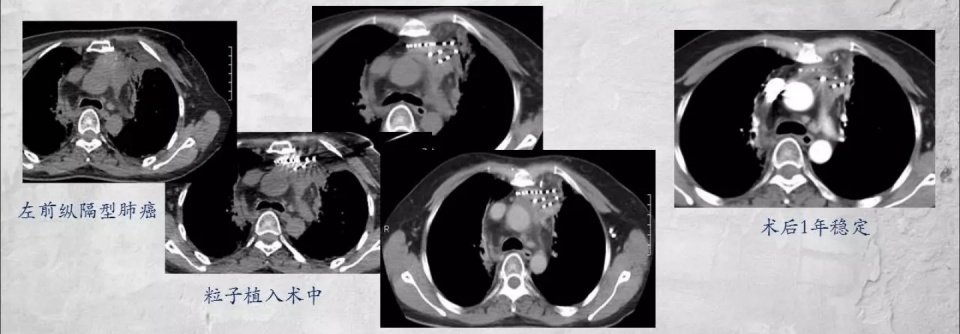

像这位女士,因为晚期肺癌剧烈胸疼,而且广泛黏连大血管,已经不能手术。

通过放射性粒子植入,既缓解疼痛,改善生活质量,也延长了寿命。